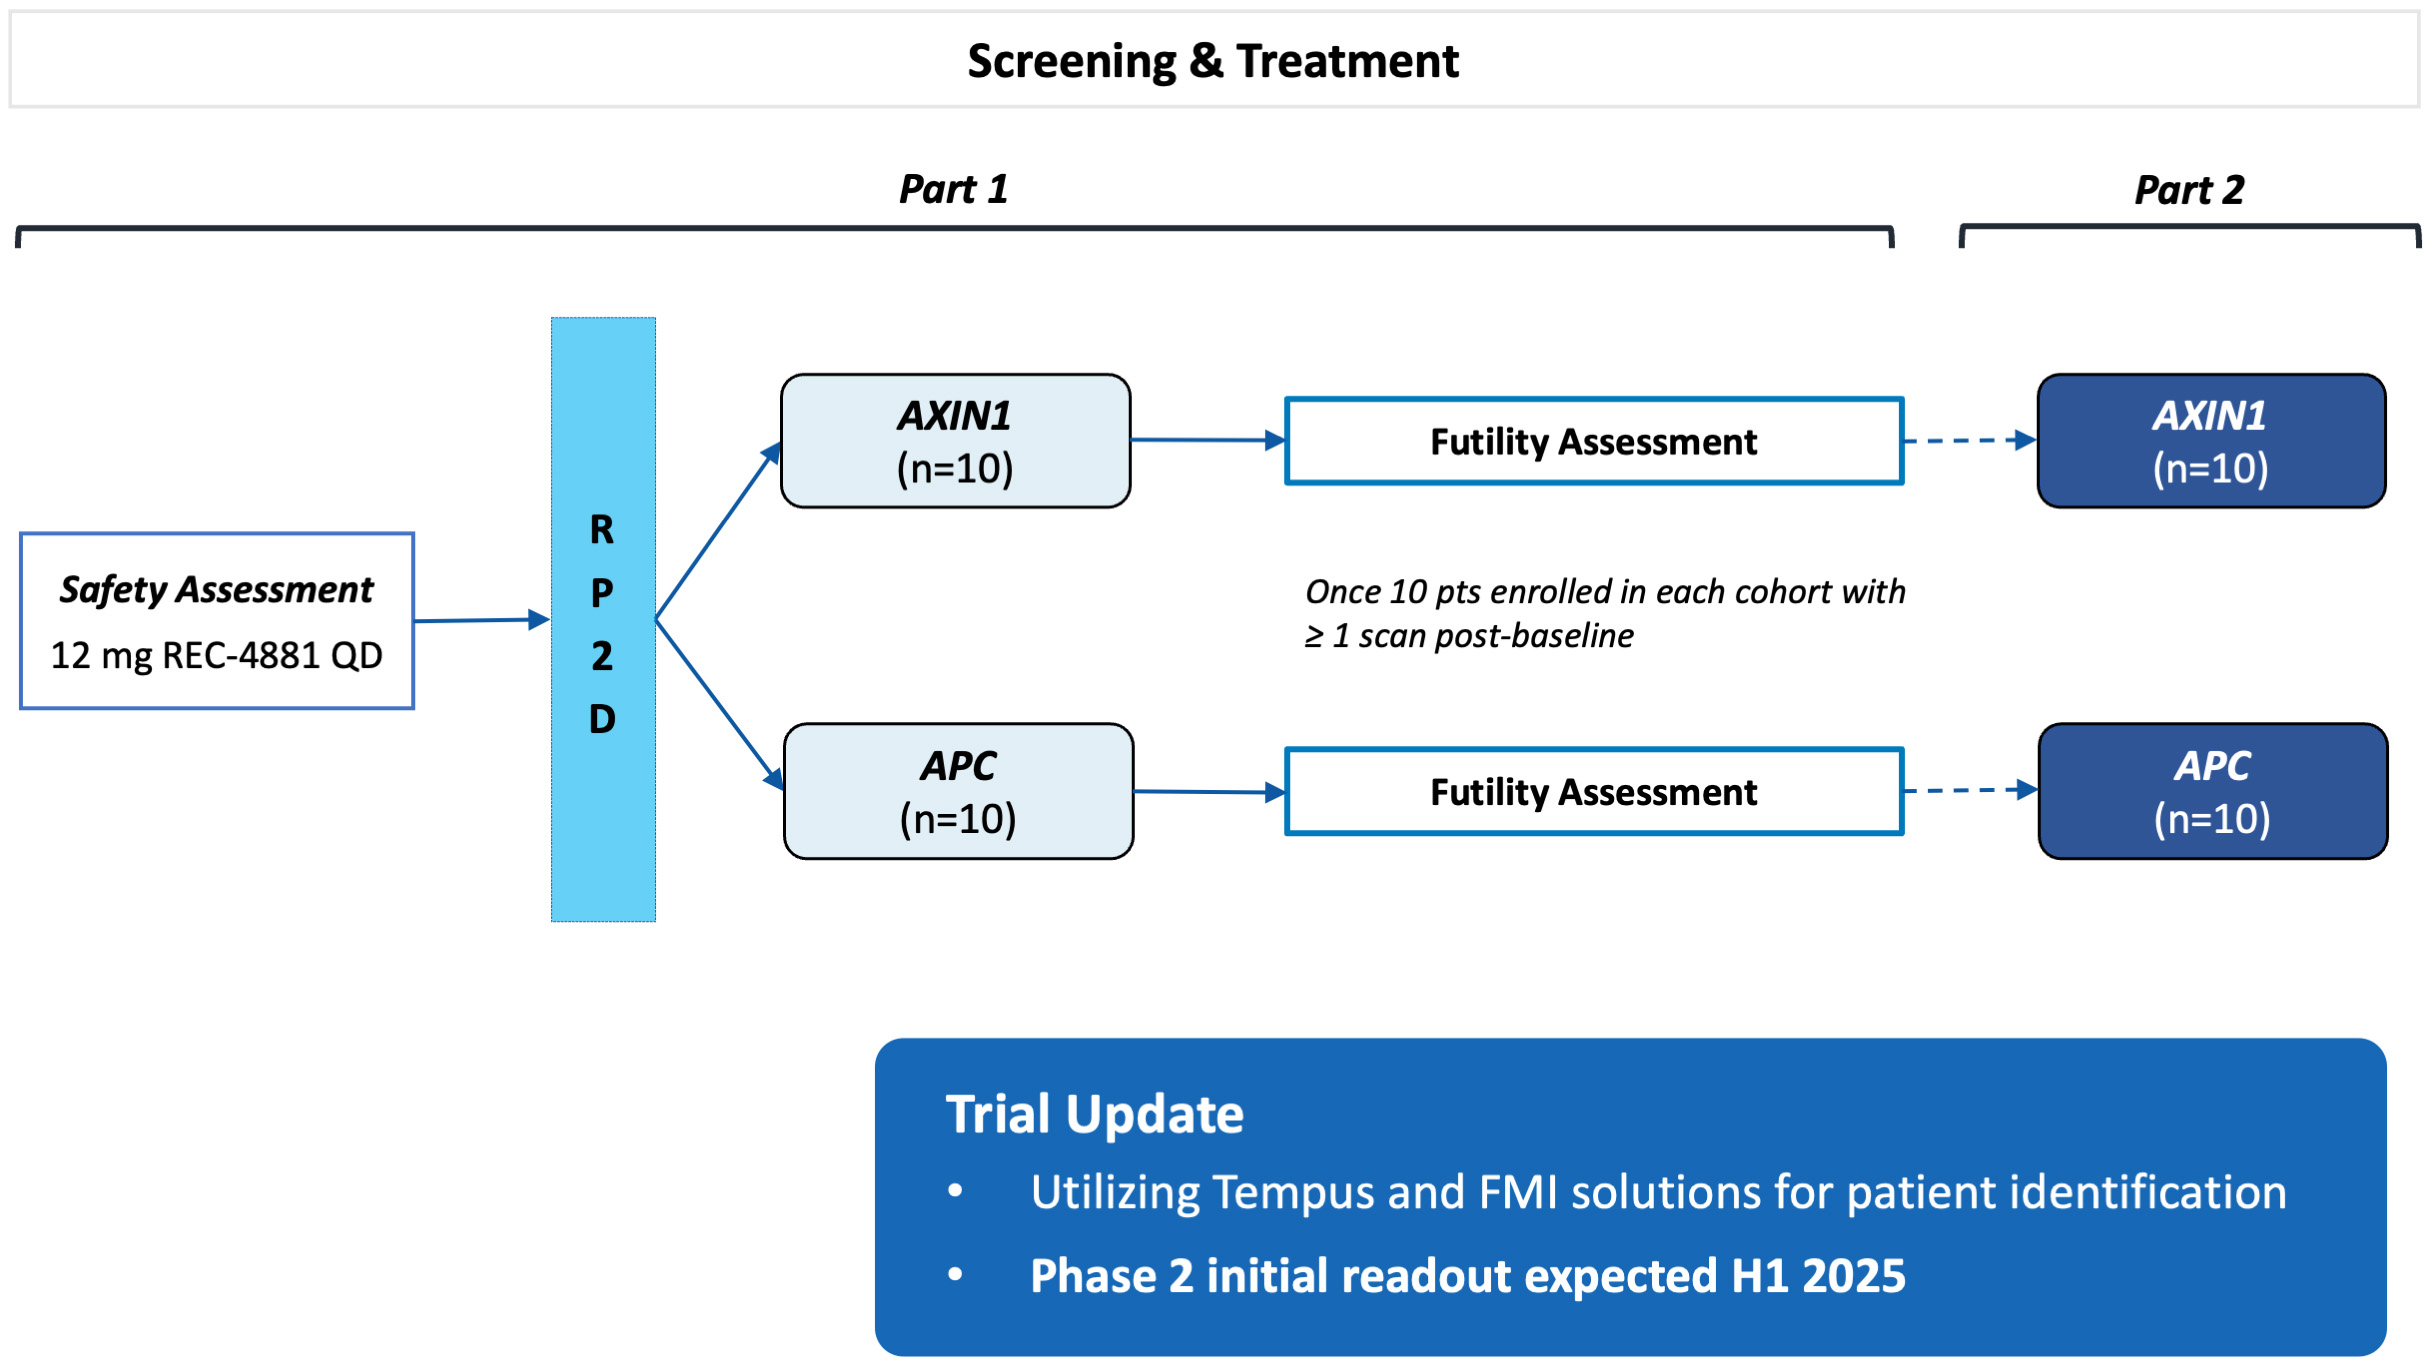

•Five phase 2 clinical-stage programs with multiple upcoming data readouts expected, including REC-994 in cerebral cavernous malformation (CCM) in Q3 2024, REC-2282 in neurofibromatosis type 2 (NF2) in Q4 2024, REC-4881 in familial adenomatous polyposis (FAP) in H1 2025, and REC-4881 in AXIN1 or APC mutant solid tumors in H1 2025